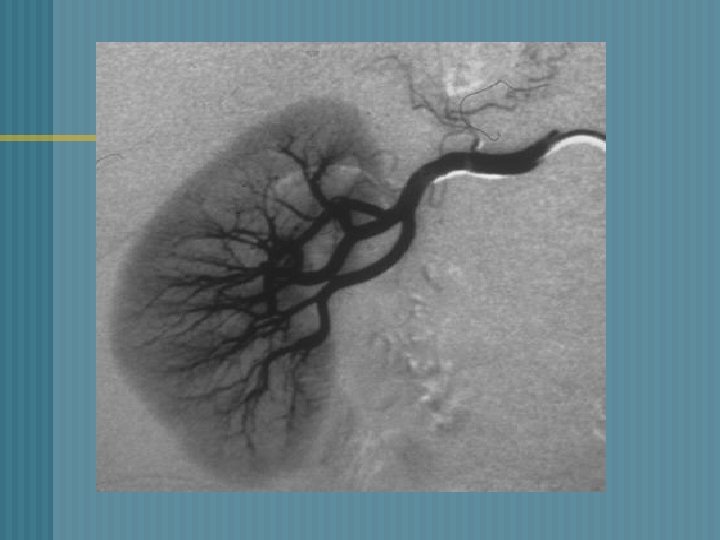

RENAL ANGIOGRAPHY n o o o § 1. 2. 3. RENAL ANGIOGRAM: Catheter inserted into femoral artery Contrast material injected through the catheter Visualize renal blood vessels Findings : Renal artery stenosis Differentiate renal cysts from tumors Evaluate hypertension